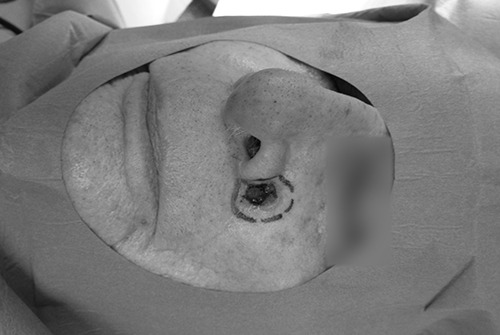

La chirurgie dermatologique fait appel à des techniques de traitement précises. En effet, en dehors des cas de mélanome qui représentent une maladie grave, la plupart des lésions cutanées peuvent être guéries définitivement. Il est donc nécessaire de prendre toutes les précautions, en respectant les marges de sécurité nécessaires (variable en fonction du type de lésion) pour retirer définitivement la lésion.

Il arrive parfois que l’acte soit une simple exérèse en pleine épaisseur de peau avec suture bord à bord. C’est une intervention simple, rapide et efficace ne nécessitant pas de préparation et de réflexions techniques préalables. Dans d’autres cas nous devons faire appel à des techniques de réparation chirurgicale sophistiquées très variées en fonction de la localisation de la lésion initiale. Il peut s’agir de lambeaux cutanés d’avancement, de lambeaux de rotation ou bien de greffes libres qui nécessitent une réflexion technique de la part du chirurgien esthétique qualifié, afin d’obtenir un résultat le plus discret possible.

Dans tous les cas de figure, l’analyse systématique de toutes les lésions cutanées est obligatoire.